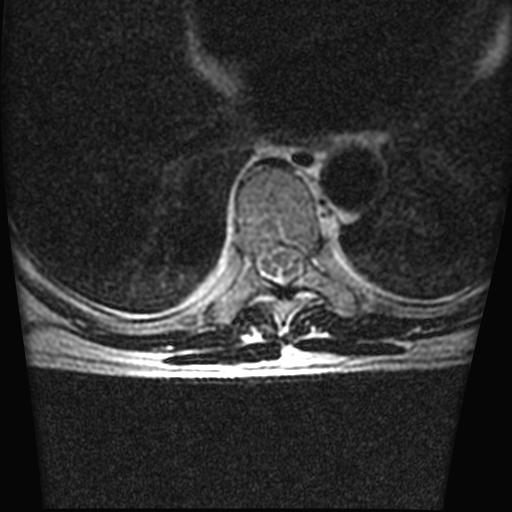

标题: MRI0985:胸椎.68岁男性,胸部疼痛,

68岁男性,胸部疼痛,不适。

胸7椎体楔状变形及信号异常,附件未见明显异常信号.椎间隙正常.未见软组织块影.考虑骨质疏松所致压缩性骨折可能大.

胸7椎体楔状变形及信号异常[t1t2 均为低信号],附件未见明显异常信号.椎间隙正常.未见软组织块影.考虑陈旧性压缩性骨折伴退变。

首先需除外单发成骨性转移瘤可能。